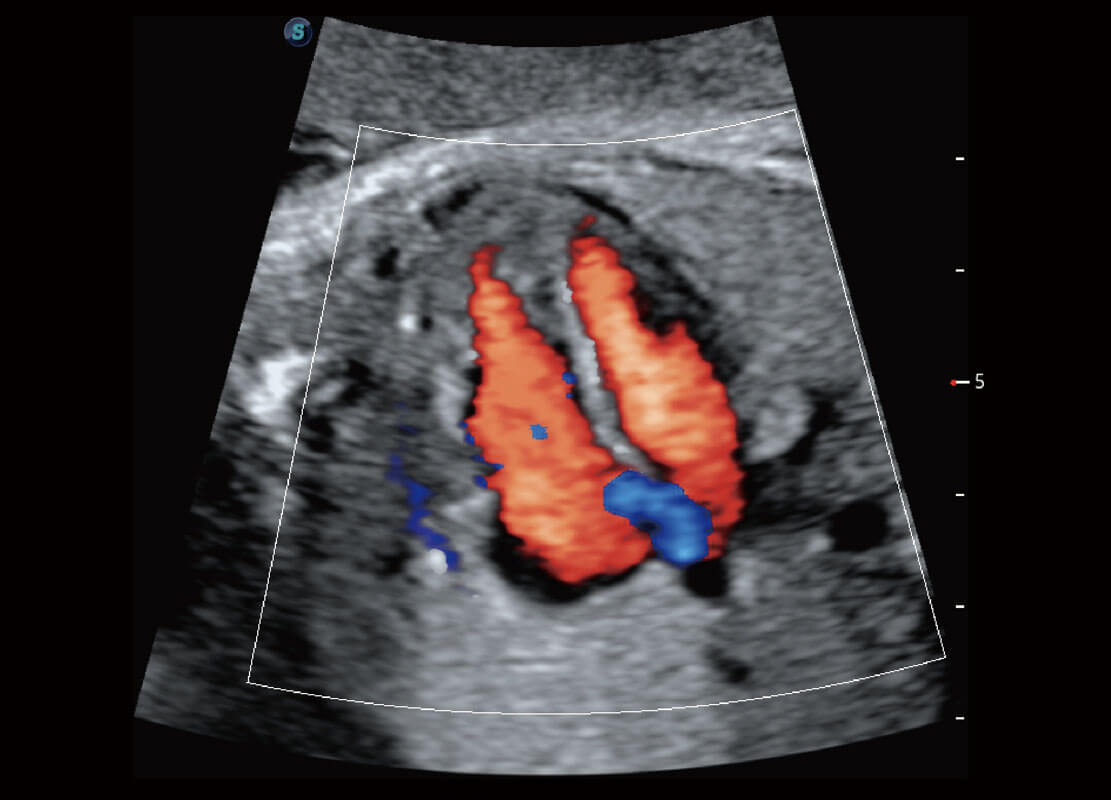

胎儿体循环

四腔切面

四腔心血流

右室双出口

胎心容积成像